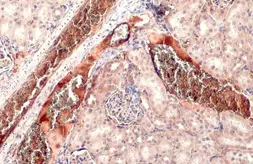

Images